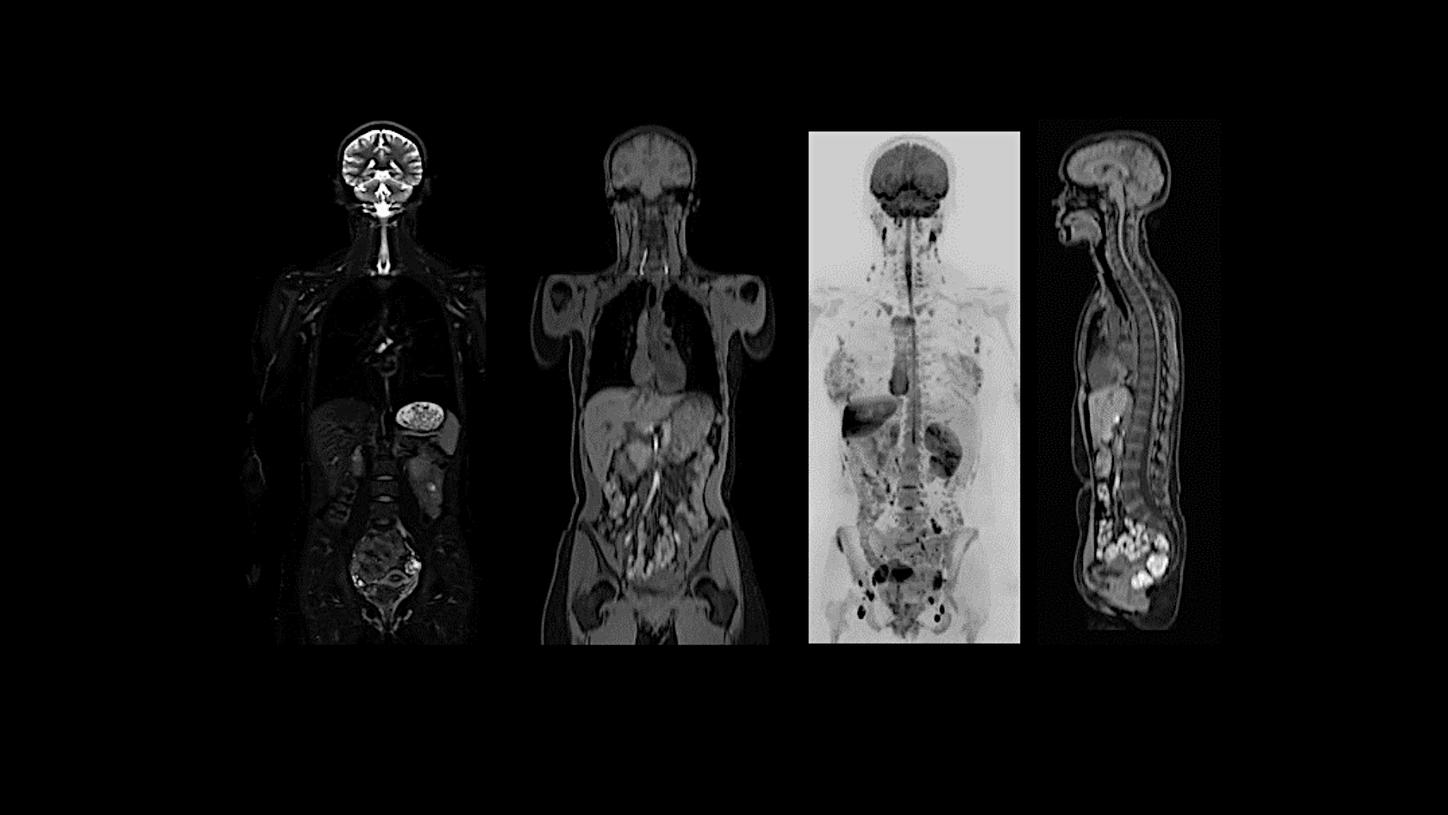

Clinical excellence from head to toe​

MAGNETOM Flow. Platform is designed to deliver highest-quality imaging for every clinical discipline. From routine imaging and screening to advanced imaging, from head to toe and from cardiac to oncology cases, it is planned to adapt to a wide range of imaging needs. Regardless of the type of institution, throughput demand, or clinical specialty, MAGNETOM Flow. Platform will empower you to achieve clinical excellence.